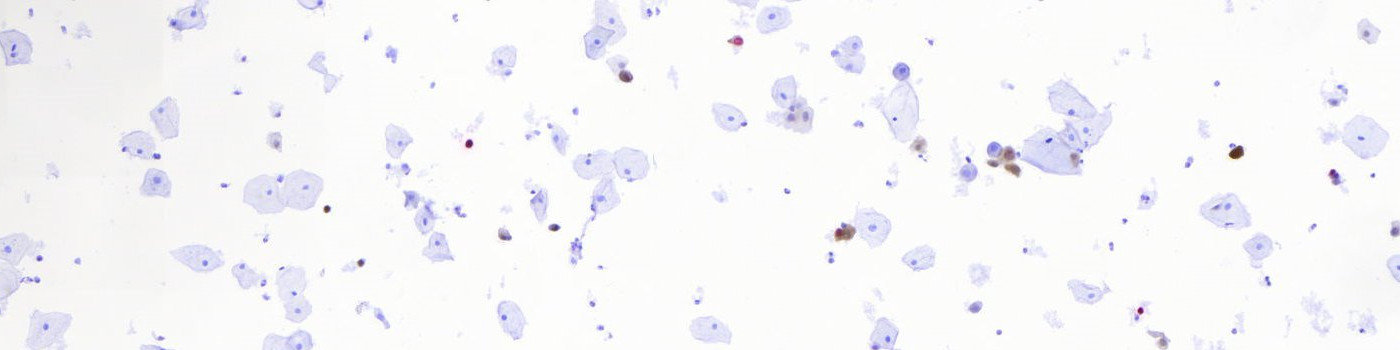

The APP identifies regions of interests (ROIs) based on the p16 (DAB), Ki-67 (Fast Red) and Hematoxylin color-deconvolution bands. The color-deconvolution bands are used as input parameters to a naïve Bayesian classifier that identifies positively stained nuclei and their cytoplasm as well as negative cells. A ROI is then automatically created around the positively stained cells only, so that further processing of the image is limited to be within this area making the processing time considerably faster (see FIGURE 1 and 2).